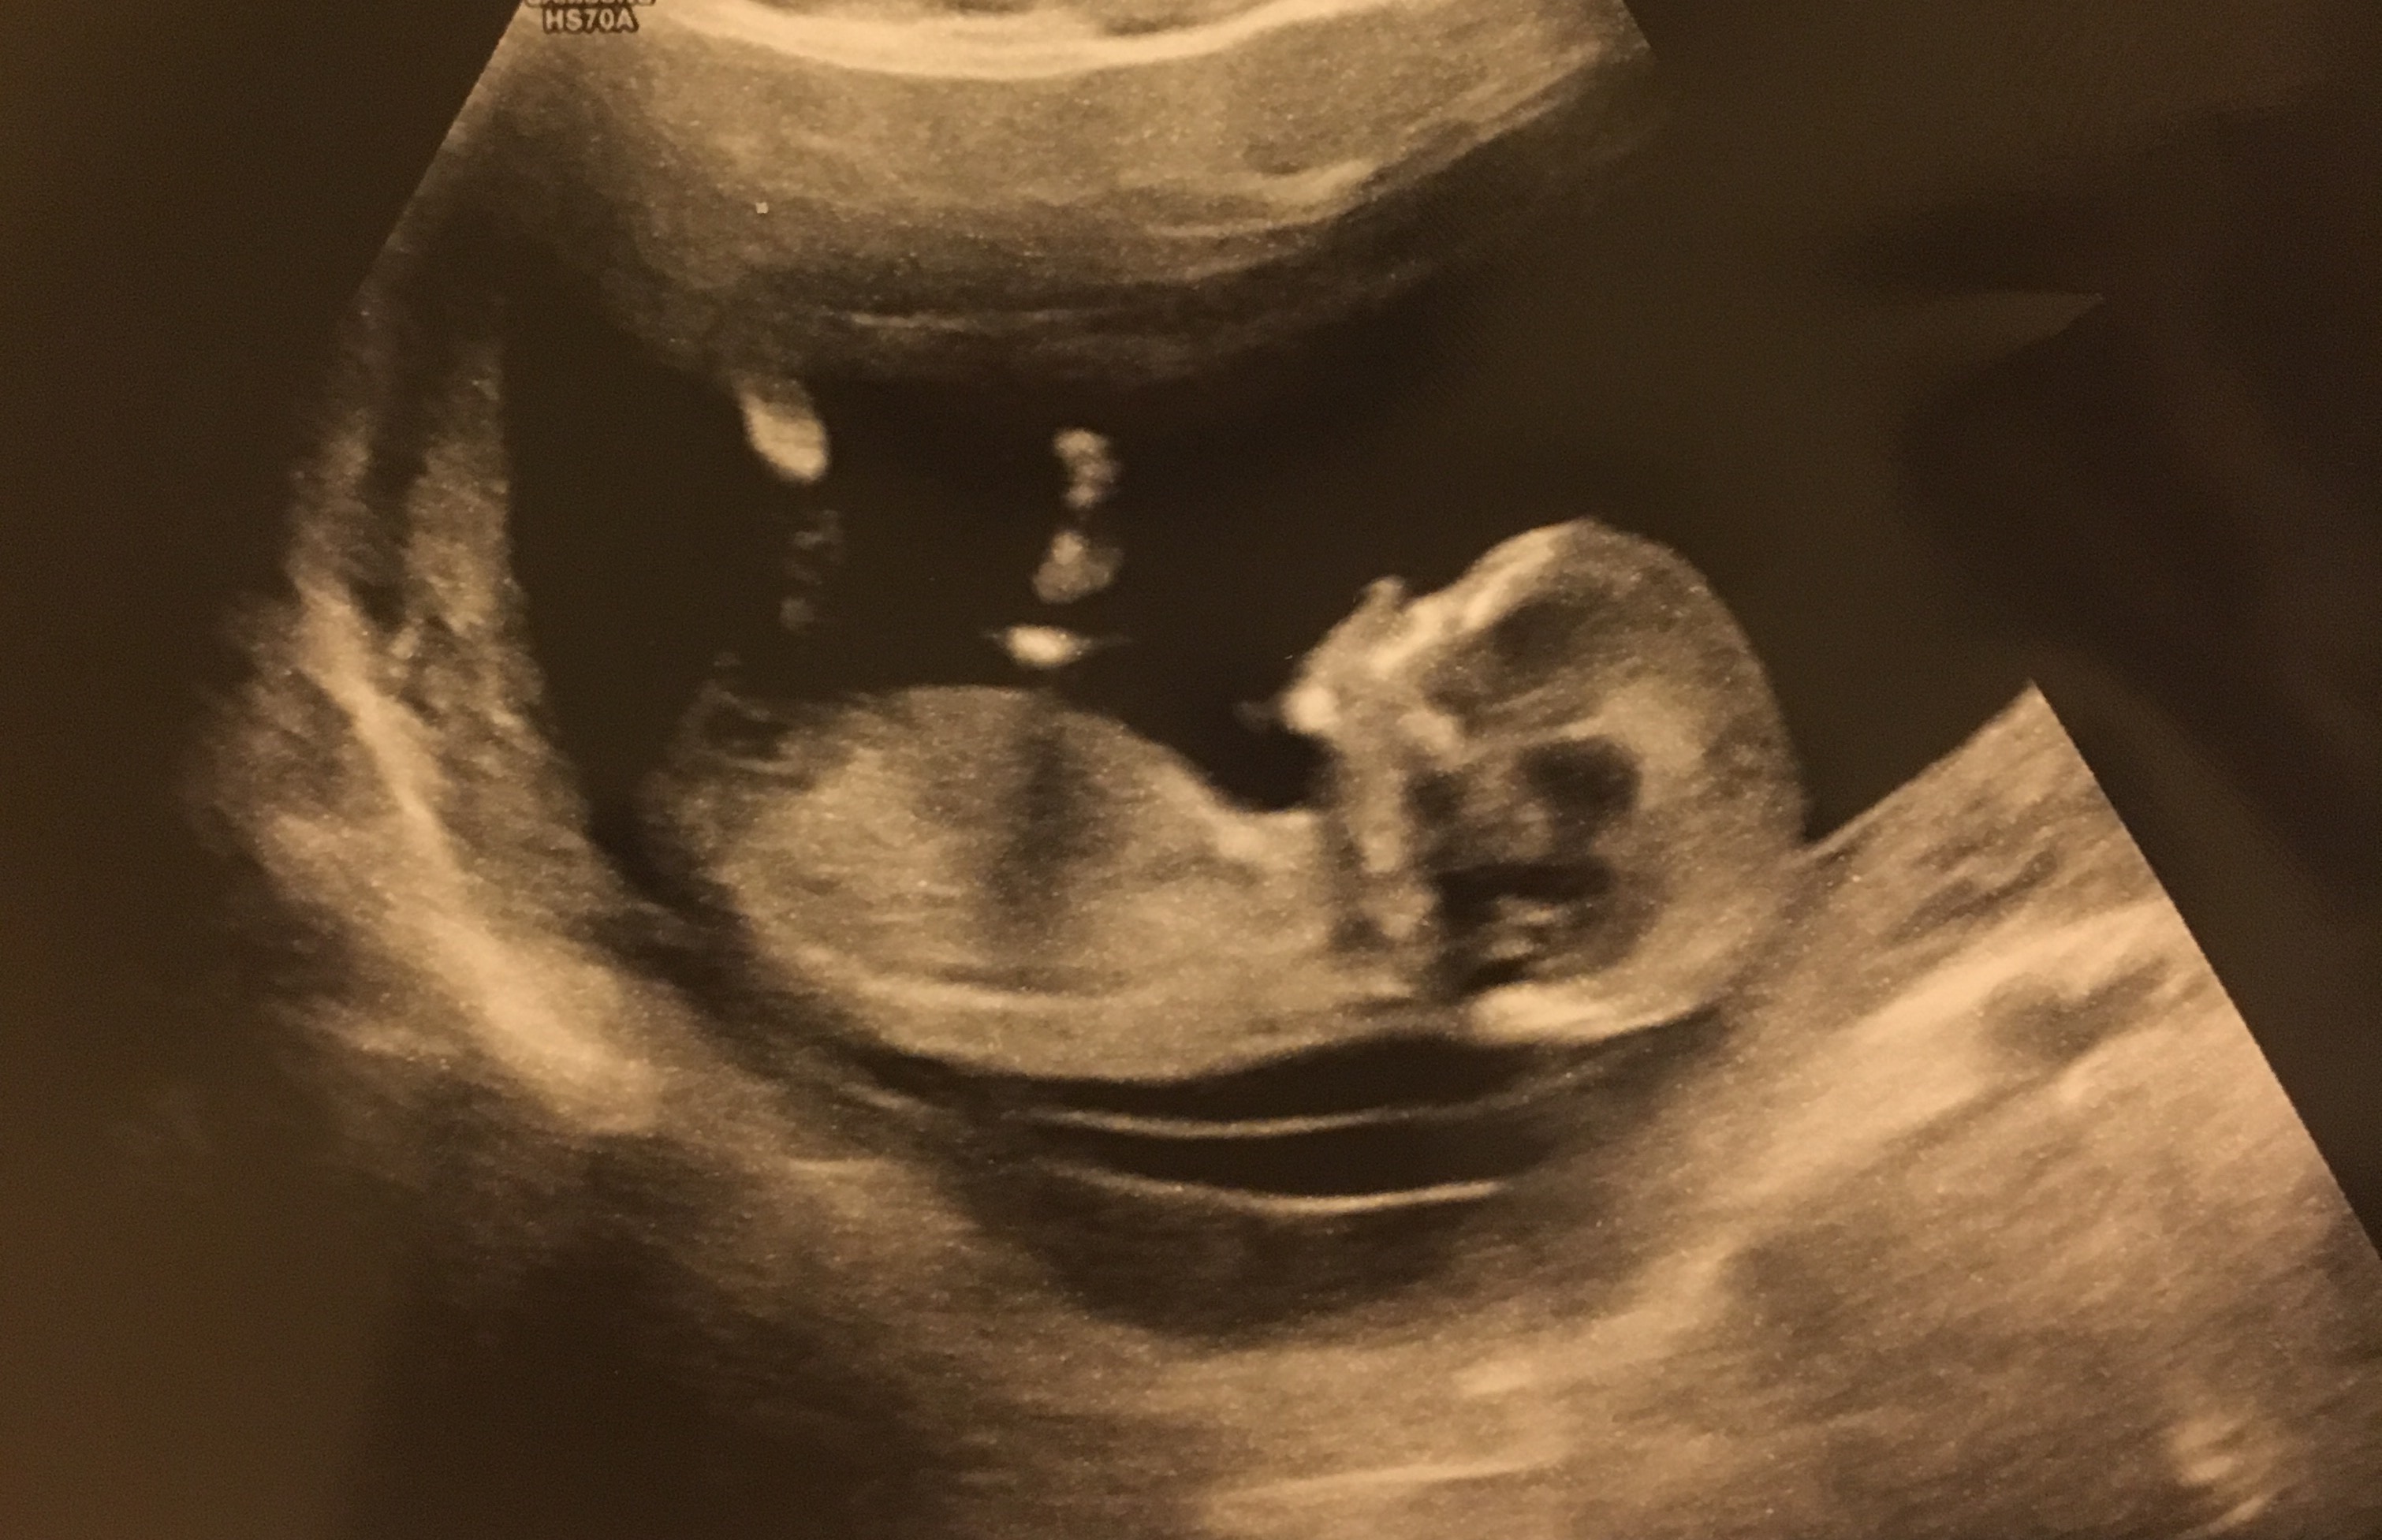

Can anyone make a guess at the gender from these pics? Taken at 13 weeks! Attachment 36381Attachment 36382